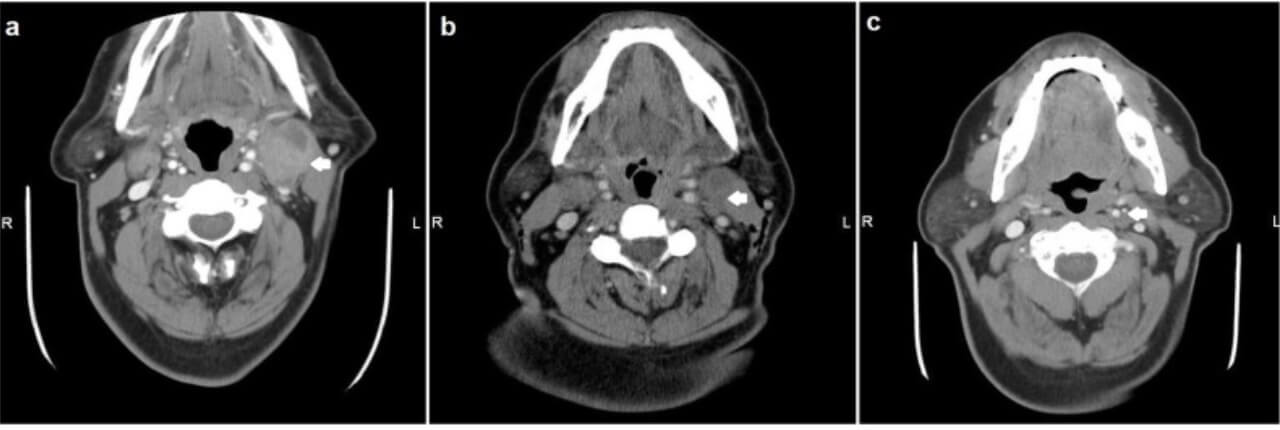

- Computed tomography (CT scan). Critical for tumour imaging.

Take a story of a 62-year-old male diagnosed with stage 3 gingival squamous cell carcinoma (GSCC) during biopsy of a gingival ulcer. He was offered treatment for gum cancer in Germany and underwent the procedure called intra-arterial chemotherapy infusion, which is an innovative treatment of head and neck tumors. The patient completed several cycles of treatment, experiencing only mild side effects. During follow-up, significant tumor regression and pain control were achieved. The patient also preserved speech and chewing, allowing him to maintain his quality of life.

The diagnostic tests, such as biopsy and imaging (CT, PET scan), are performed to determine tumor stage and potentially mouth tumor metastasis.